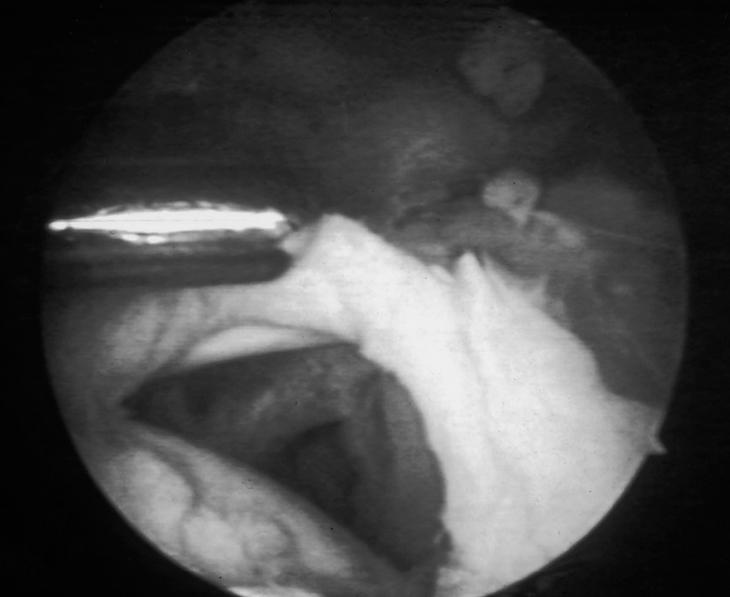

La acromioplastia por vía artroscópica fue descrita por Ellman16 para los estadios II y III de Neer (fig. 3), dando a conocer los resultados preliminares de las primeras descompresiones subacromiales por artroscopia, en las que se reseca la superficie anteroexterna del acromion, se efectúa una bursectomía en los pacientes más jóvenes, y se desinserta el ligamento coracoacromial.

Figura 3. Delimitación del ligamento coracoacromial con dos agujas según la técnica de Ellman.